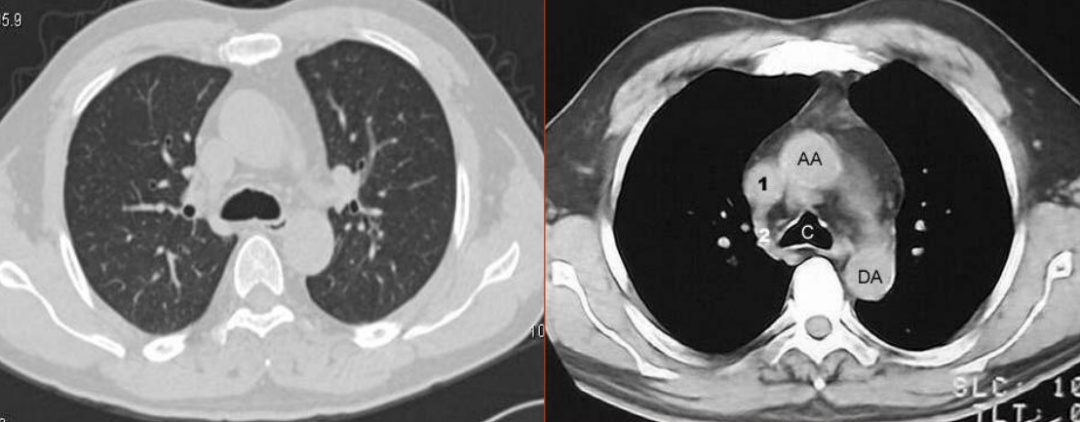

(胸部ct图像)

CT全称是Computed Tomography(计算机断层成像),与普通X线一样,都是以X线穿透人体为基础,不过是分层连续扫描,形成断层图像,没有重叠,能看清楚器官之间的空间位置关系,也可以通过计算机进行后处理,得到曲面重组、最大密度投影法、容积再现技术、CTA等不同应用的图像。缺点是:辐射剂量相对大,价格贵。

曲面重组图像

最大密度投影